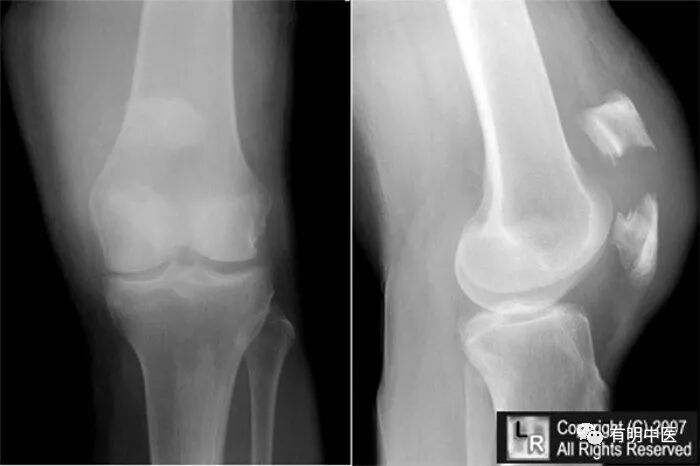

髌骨骨折后,局部有淤血肿胀痛,伤处压痛明显。横断形触之有沟槽或有骨擦音,膝关节不能伸屈,功能障碍。直腿勉强能走,但不能持久。X线片有助诊断。